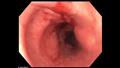

وتم إدخال كاميرا في الجهاز الهضمي السفلي للمرأة حيث تم اكتشاف طقم الأسنان في معدتهان ثم تم إزالة المنظار الداخلي وإعادة إدخاله مع غطاء واقٍ لغطاء جسم غريب متصل بالطرف.

وبعد عدة محاولات، تمكن الأطباء من وضع واقي غطاء المحرك فوق طقم الأسنان وإمساكه بملقط أسنان الفئران، وإزالة الجسم الغريب من معدة المرأة.